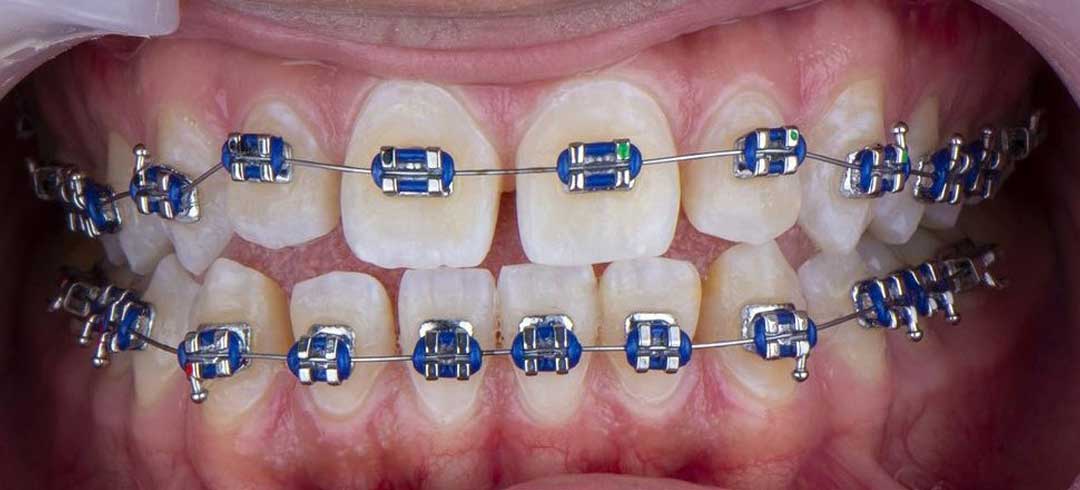

- Orthodontics